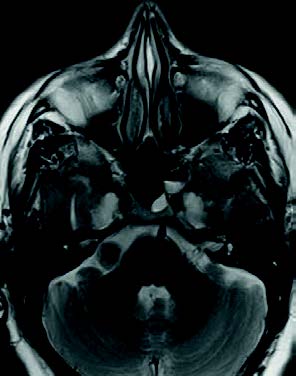

Mujer de 76 años con un traumatismo craneal y pérdida de conciencia. Cuatro meses antes le detectaron en un TAC craneal una formación calcificada en ángulo pontocerebeloso.

Mujer de 76 años con un traumatismo craneal y pérdida de conciencia. Cuatro meses antes le detectaron en un TAC craneal una formación calcificada en ángulo pontocerebeloso. Tiene antecedentes de vértigos posicionales desde hace años por problemas de columna. Fue operada de una tumoración lipomatosa grande en la espalda hace 2 años y desde entonces tiene una contractura. Refiere pérdida de audición antigua, más intensa por oído derecho, y ahora también tiene pérdida de olfato.

En la exploración, los tímpanos son normales y la audiometría presenta una hipoacusia sensorial bilateral de 50 dB de media en OD y de 45 dB en OI, con caída en agudos. Se pide RMN craneal.